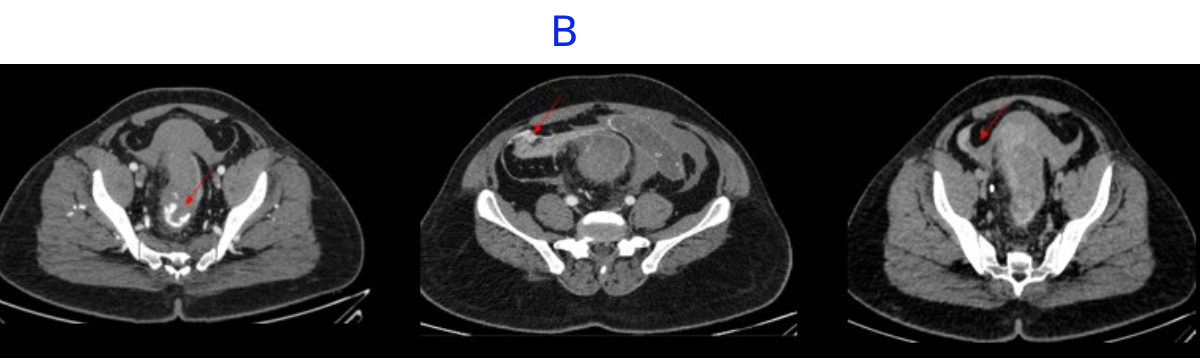

B. LEGENDS

- Distal rectum and proximal sigmoid colon mild edematous wall thickening.

- Hemorrhagic fluid noted in bilateral paracolic gutter and pelvis with active contrast extravasation.

- Omentomesenteric fat stranding in lower abdomen with mesorectal fascial thickening noted.